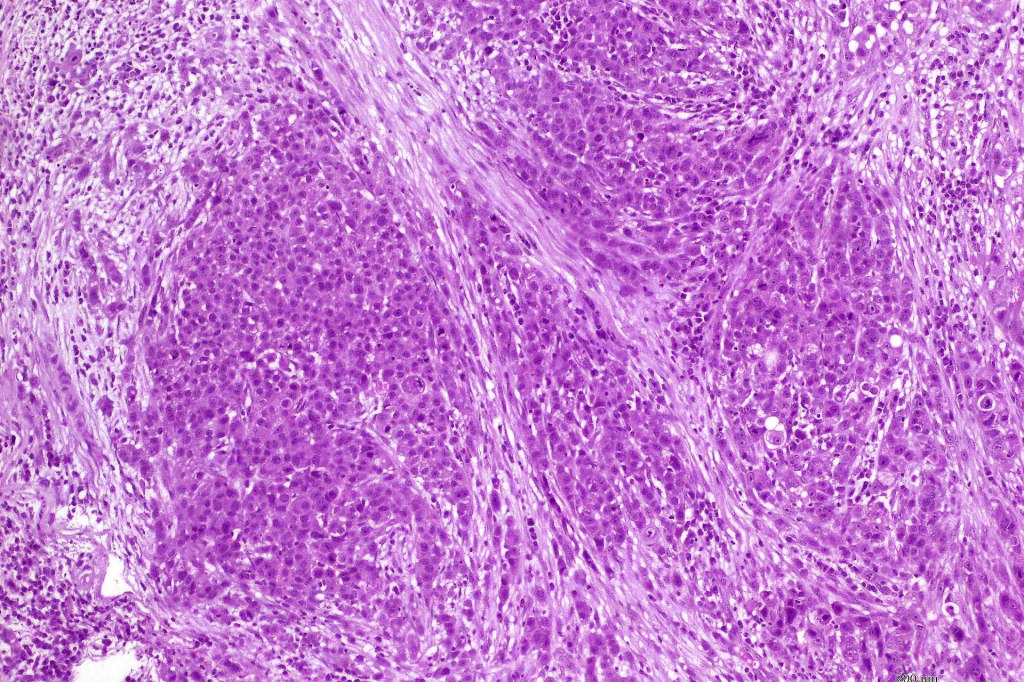

Histological features

•Poorly circumscribed tumor nodule with invasive border

•Rarely cystic

•Variable glandular, tubular, papillary, tubulo-papillary, diffuse and solid growth patterns

•Variable necrosis